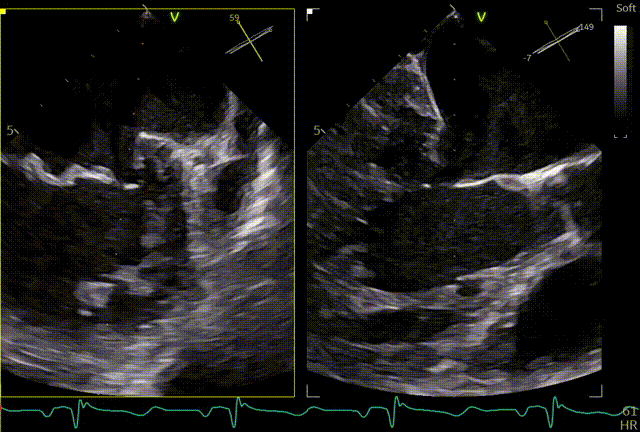

术前TTE

两腔心

短轴

四腔心zoom模式